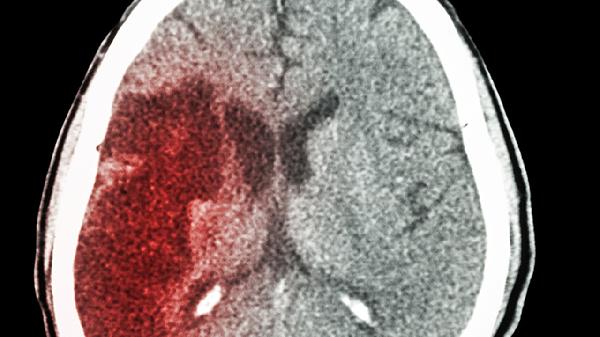

脑出血后遗症患者可遵医嘱使用阿司匹林肠溶片、胞磷胆碱钠片、尼莫地平片、甲钴胺片、长春西汀片等药物。脑出血后遗症多与脑组织损伤、神经功能缺损有关,需根据具体症状选择改善脑循环、营养神经或抗血小板聚集的药物。

脑出血后遗症患者需在神经内科医生指导下规范用药,避免自行调整剂量。日常应保持低盐低脂饮食,控制血压血糖在稳定水平,循序渐进进行肢体功能康复训练。定期复查头颅CT或MRI评估恢复情况,出现头痛加剧、肢体无力等症状需立即就医。注意保持情绪稳定,保证充足睡眠,避免用力排便或剧烈咳嗽等可能引起颅内压增高的行为。